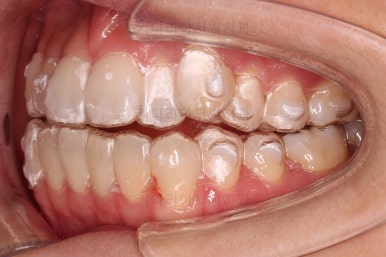

1. 초진

초진 시 입안의 모습입니다.

덧니가 눈에 띄고요.

맞물림이 긴밀하지 못한 상태였습니다.

전반적으로 약간 삐뚤지만 많이 심하다고 보긴 힘들었습니다.

장치를 착용한 사진입니다.

투명한 플라스틱 시트가 치아를 감싸면서 미세하게 움직이는 힘을 주는 장치인데요.